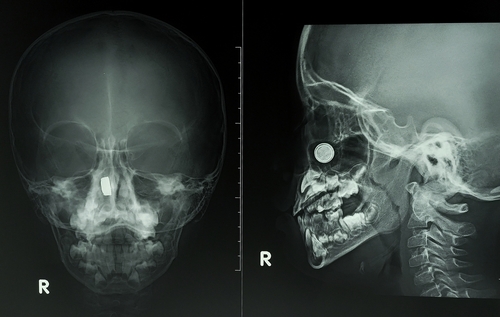

В протоколе диагностического исследования врач описывает состояние околоносовых пазух, голосовых связок, костных структур, лимфоидного кольца. Специалист сравнивает показатели с нормой, выявляет различные изменения. Помимо этого, рентгенолог отражает видимые патологии и их характеристики. В конце пишет заключение и рекомендации.

Рентгенограмма носоглотки поможет выявить переломы костей, доброкачественные новообразования и воспалительные процессы околоносовых пазух, повреждения пазух носа, патологические процессы органа слуха, деформации носовой перегородки, аденоиды и иное разрастание лимфоидной ткани. Диагностика информативна в плане визуализации посторонних предметов, онкологических процессов, мукоцеле, пиоцеле, полипозных разрастаний, инфекционных заболеваний, кист, метастатических очагов.

Что показывает рентген носоглотки в боковой проекции?

Процедура отличается высокой информативностью и дает возможность изучить текущее состояние носоглотки. В большинстве случаев данная методика осуществляется в боковой проекции. На получаемых снимках хорошо визуализируется язык, свод носоглотки, вход в гортань. По изменению изучаемых структур доктор затем выявляет возникшие проблемы и их особенности.